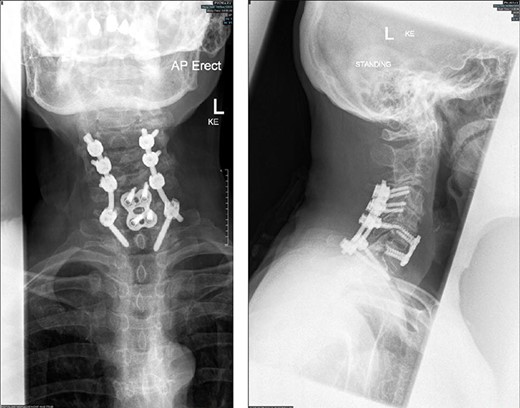

Radiographs (antero-posterior and lateral views) of the cervical spine following instrumentation.

approach was performed to reconstruct the anterior column using an anterior cervical discectomy and fusion through the C6/7 disc space. This was performed with a CeSPACE cage (B Braun, Hessen, Germany) and a Venture anterior cervical locking plate (Medtronic, Minneapolis, MN, USA). The patient was then turned prone and a posterior approach to the spine was performed. An instrumented fusion was performed using lateral mass screws in C4, C5 and C6 and pedicle screws in T1 bilaterally using Mountaineer (Depuy Synthes, Raynham, MA, USA). Grafton bone graft substitute (Medtronic, Minneapolis, MN, USA) was used in both the anterior and posterior stages.

She made a good post-operative recovery, and the upper limb neurological symptoms resolved. Post-operative radiographs are shown in Fig. 5.